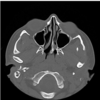

Ny information: En måned senere kommer forældrene igen. Barnet har fået gennemført en CT scanning af næse og bihuler. Forældrene har billedet med og de fortæller at ØNH-lægerne konstaterede at venstrenæsehule er blindlukket bagtil. Se nedenstående axiale billede, der er repræsentativt for tilstanden. Forældrene vil gerne have svar på nogle spørgsmål.

C. Hvad hedder tilstanden?

Choanal atresi

Ny information: En måned senere kommer forældrene igen. Barnet har fået gennemført en CT scanning af næse og bihuler. Forældrene har billedet med og de fortæller at ØNH-lægerne konstaterede at venstrenæsehule er blindlukket bagtil. Se nedenstående axiale billede, der er repræsentativt for tilstanden. Forældrene vil gerne have svar på nogle spørgsmål.

C. Hvad hedder tilstanden? ⇒ Choanal atresi

D. Er det medfødt eller skyldes det et slag på næsen?

Det er medfødt.

Ny information: En måned senere kommer forældrene igen. Barnet har fået gennemført en CT scanning af næse og bihuler. Forældrene har billedet med og de fortæller at ØNH-lægerne konstaterede at venstrenæsehule er blindlukket bagtil. Se nedenstående axiale billede, der er repræsentativt for tilstanden. Forældrene vil gerne have svar på nogle spørgsmål.

- C. Hvad hedder tilstanden? ⇒ Choanal atresi*

- D. Er det medfødt eller skyldes det et slag på næsen?*

- ⇒ Det er medfødt.*

E. Hvordan skal det behandles?

Kirurgi i 4-6 års alderen

Ny information: En måned senere kommer forældrene igen. Barnet har fået gennemført en CT scanning af næse og bihuler. Forældrene har billedet med og de fortæller at ØNH-lægerne konstaterede at venstrenæsehule er blindlukket bagtil. Se nedenstående axiale billede, der er repræsentativt for tilstanden. Forældrene vil gerne have svar på nogle spørgsmål.

- C. Hvad hedder tilstanden? ⇒ Choanal atresi*

- D. Er det medfødt eller skyldes det et slag på næsen?*

- ⇒ Det er medfødt.*

F. Tilstanden er ensidig hos din patient, men hvad ville der være sket, hvis den var dobbeltsidig? (max 20 ord)

Dobbeltsidig Choanal atresi giver akut vejrtrækningsbesvær og skal behandles akut med kirurgi indenfor de første levedøgn.